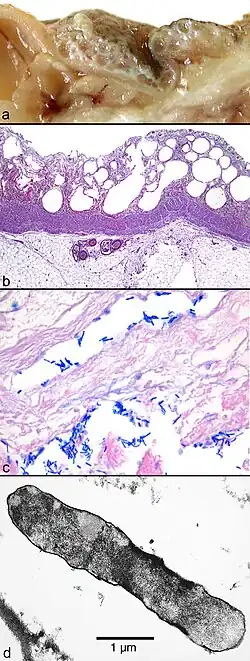

(a) Macroscopic picture of the edematous intestinal wall with multiple submucosal and subserosal cysts

(b) Histological picture of the intestinal mucosa with nonreactive necrosis

(c) Gram stain of cysts with large, rod-shaped bacteria

(d) Electron microscopic picture of a bacterium found in a submucosal cyst